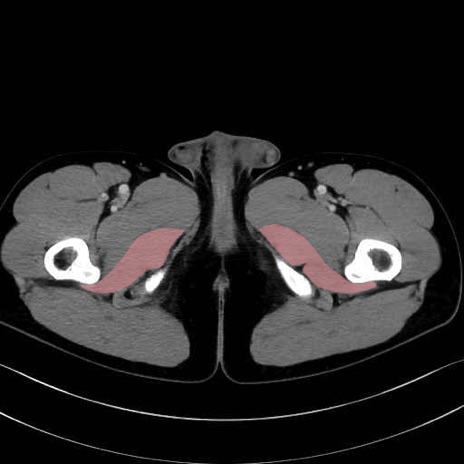

大内転筋(Adductor magnus)、小内転筋(Adductor minimus) のCT画像の解剖

大内転筋・小内転筋 (Adductor magnus / Adductor minimus)